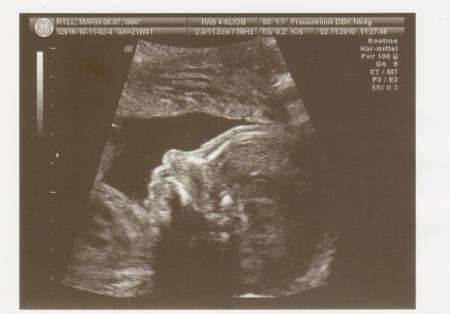

Hallo ihr Lieben, ich bin ganz begeistert Feinsono war echt toll! Es bleibt 100% beim Mädchen-Outing und es gab keine Auffälligkeiten!!! Sie sagte das es ein zierliches Mädchen ist, aber alle Werte sind im Normbereich. Aber mein Mann und ich sind ja auch weder groß noch kräftig gebaut. Sie ist jetzt 24,8cm groß und 367gr schwer. Der werdende Papa ist auch hin und weg. Hab ganz viele Bilder bekommen. Ein paar hänge ich euch mal an. liebe Grüße